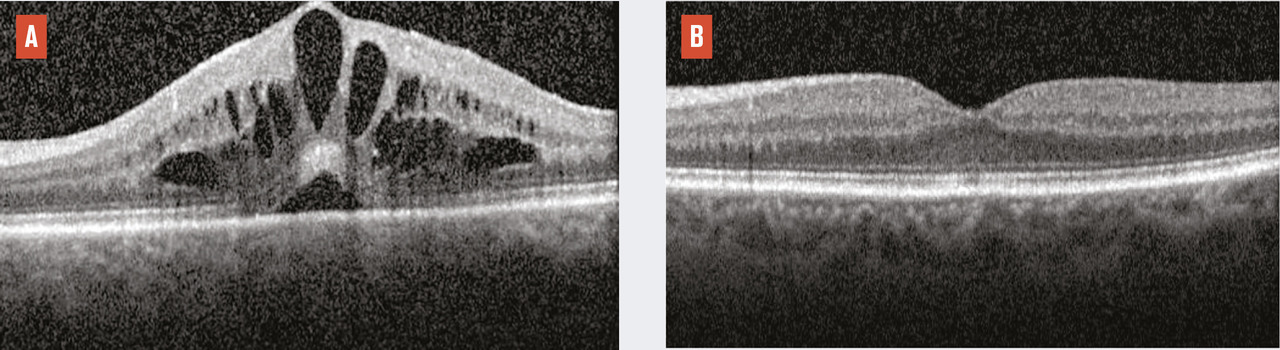

Plus rares que les uvéites antérieures, les non infectious non anterior uveitis (NINAU) sont aussi celles qui engagent le plus fréquemment le pronostic visuel. En effet, le site primitif de l’inflammation est intermédiaire (vitré) ou postérieur (rétine, choroïde), donc directement susceptible d’atteinte maculaire. Or l’œdème maculaire est la première cause de baisse d’acuité visuelle irréversible au cours des uvéites (fig. 2). Le traitement des uvéites non infectieuses non antérieures est plus délicat que celui des uvéites antérieures, car les collyres n’ont pas d’effet sur les manifestations inflammatoires du segment postérieur de l’œil. Seuls les traitements par voie générale ou les traitements locaux par injection permettant une diffusion au vitré, à la rétine ou à la choroïde sont donc susceptibles d’être efficaces.